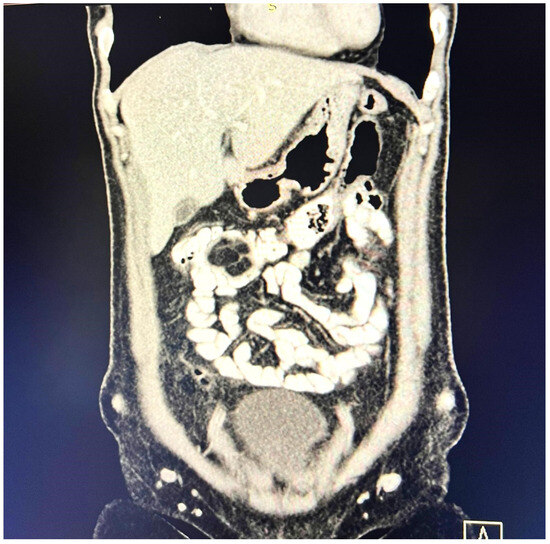

A contrast-enhanced computed tomography (CT) scan conducted on the day of admission revealed circumferential parietal thickening of a maximum of 21 mm at the hepatic flexure of the colon. This thickening extended over a length of approximately 45 mm, resulting in filiform, axial stenosis of the lumen, without any overlying distension of the colonic frame. The parietal thickening was moderately iodophilic and accompanied by discrete linear-type densification of locoregional fat, which was most likely a desmoplastic reaction. A tumor formation with a maximum axial diameter of approximately 29/28 mm, extending craniocaudal on a length of approximately 27 mm, was located at the distal end of the parietal ingrowth with an intraluminal site. This tumor formation had a polycyclic contour, thin septa within, and a discrete lodophilic peripheral appearance. It appeared to have a wide base of implantation at the level of the postero-inferior wall of the colon; mild hepatomegaly in the liver, with a homogeneous structure and a regular surface, and the absence of focal primary or secondary lesions; adenopathies in the hepatic hilum with a maximum diameter of 16/12.5 mm and in the celio-mezenteric territory with a maximum diameter of 24/19 mm; microadenopathies with the gastro-hepatic ligament; and an absence of subdiaphragmatic fluid (Figure 1, Figure 2 and Figure 3).

Figure 1. Circumferential parietal thickening noted at the hepatic flexure of the colon measuring 21/45 mm, moderately iodophilic, associated with discrete linear-type densification of locoregional fat, indicative of a desmoplastic reaction.